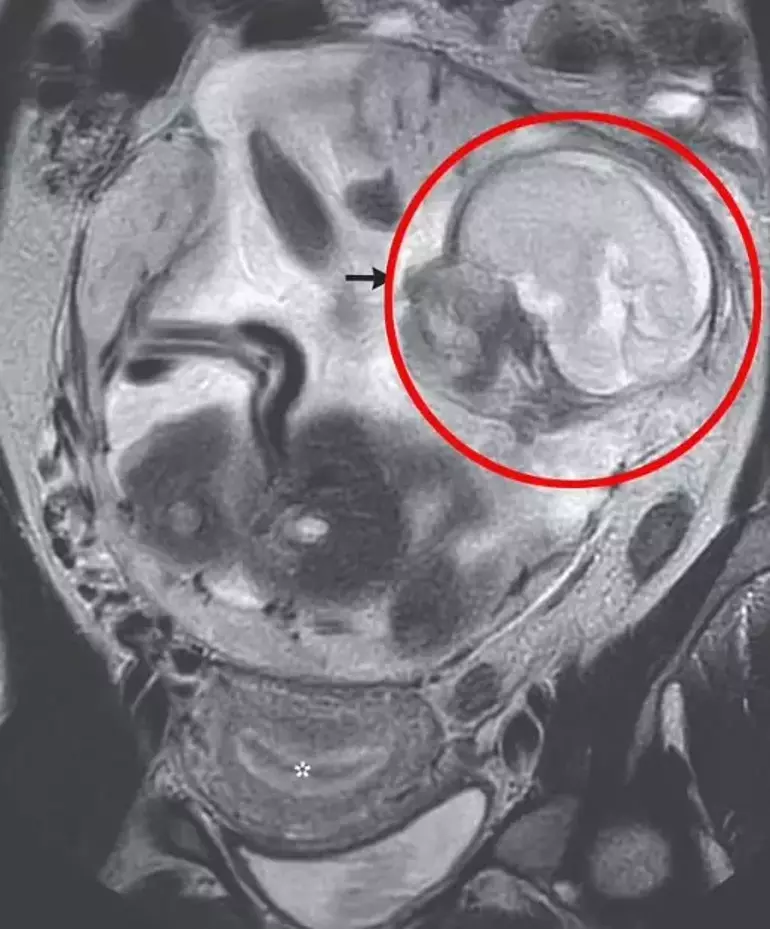

Yapılan taramalar 'normal boyda ve şekilde' bir fetüsün kadının karın boşluğunda, bağırsaklarının yanında büyüdüğünü ortaya çıkardı.

Kadının karnının kuş bakışı taraması

Bebek hayati organları tutan Periton boşluğundaydı ve plasenta pelvisin üst kısmına bağlıydı.

Dış gebelik teşhisi konan bir kadının karnında rahmin boş olduğu bebeğin ise karın boşluğunda büyüdüğü görülüyor.